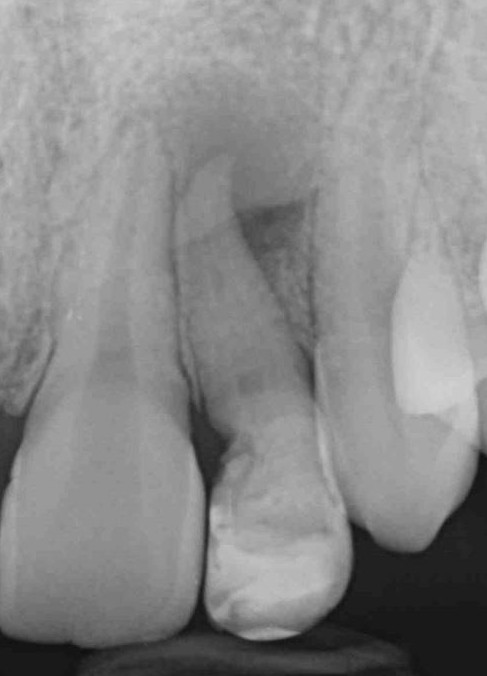

Roberta aveva avuto un trauma da piccola per cui l’incisivo da latte, a sentire lei, era risalito nella genigiva e poi era risceso dopo qualche tempo. Il dentista aveva solo saputo splintarlo e dirle che quel dente era strano e non sapeva quanto sarebbe durato.

Con tutta probabilità l’affondamento del dente da latte sulla gemma in formazione del 2.2 ha generato una deformazione dell’organo dello smalto che si è appunto invaginato all’interno della papilla dentale, formando un dens in dente, come dimostra la linea radiopaca che si intravede all’interno del dente, che non è nient’altro che smalto. Uno smalto un po’ meno mineralizzato di quello esterno, se guardiamo alla letteratura, ma pur sempre smalto.

Se non sai che il“vuoto” che vedi in centro a un dens in dente di tipo III non è il lume canalare ma semplicemente uno spazio vuoto, non riesci nemmeno a immaginare come sia fatto un dente del genere. E non riesci nemmeno a spiegarti come un dente del genere possa avere una lesione parodontale ed essere al contempo vivo, visto che quel canale non comunica col nervo ma mette solo in comunicazione il cavo orale con il parodonto!

Con l’ausilio della Cone Beam sono riuscito a identificare che il dente aveva due canali e una radice molto palatoversa: per accedere a questi canali, separati tra loro dall’istmo di smalto invaginato, potevo fare una cavità perpendicolare al dente a livello vestibolare e una palatina.